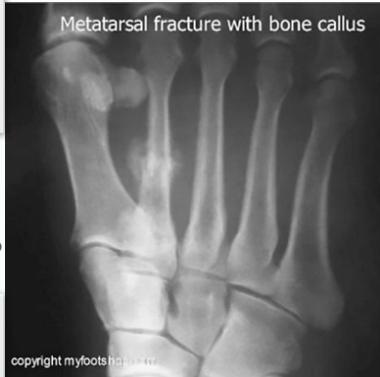

- Pathological fracture: minor trauma / strange fracture line

- Stress fracture:

- Histopathology may be confused with osteosarcoma?